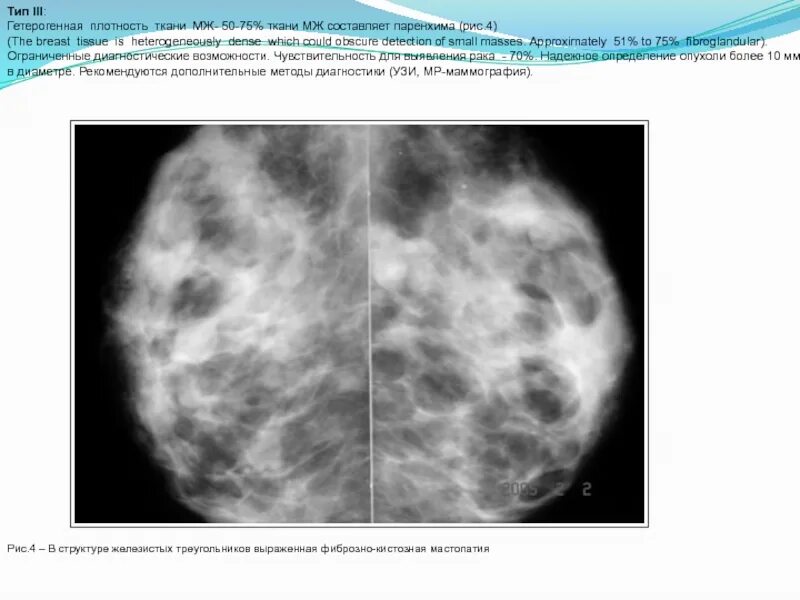

Типы плотности ткани молочных желез